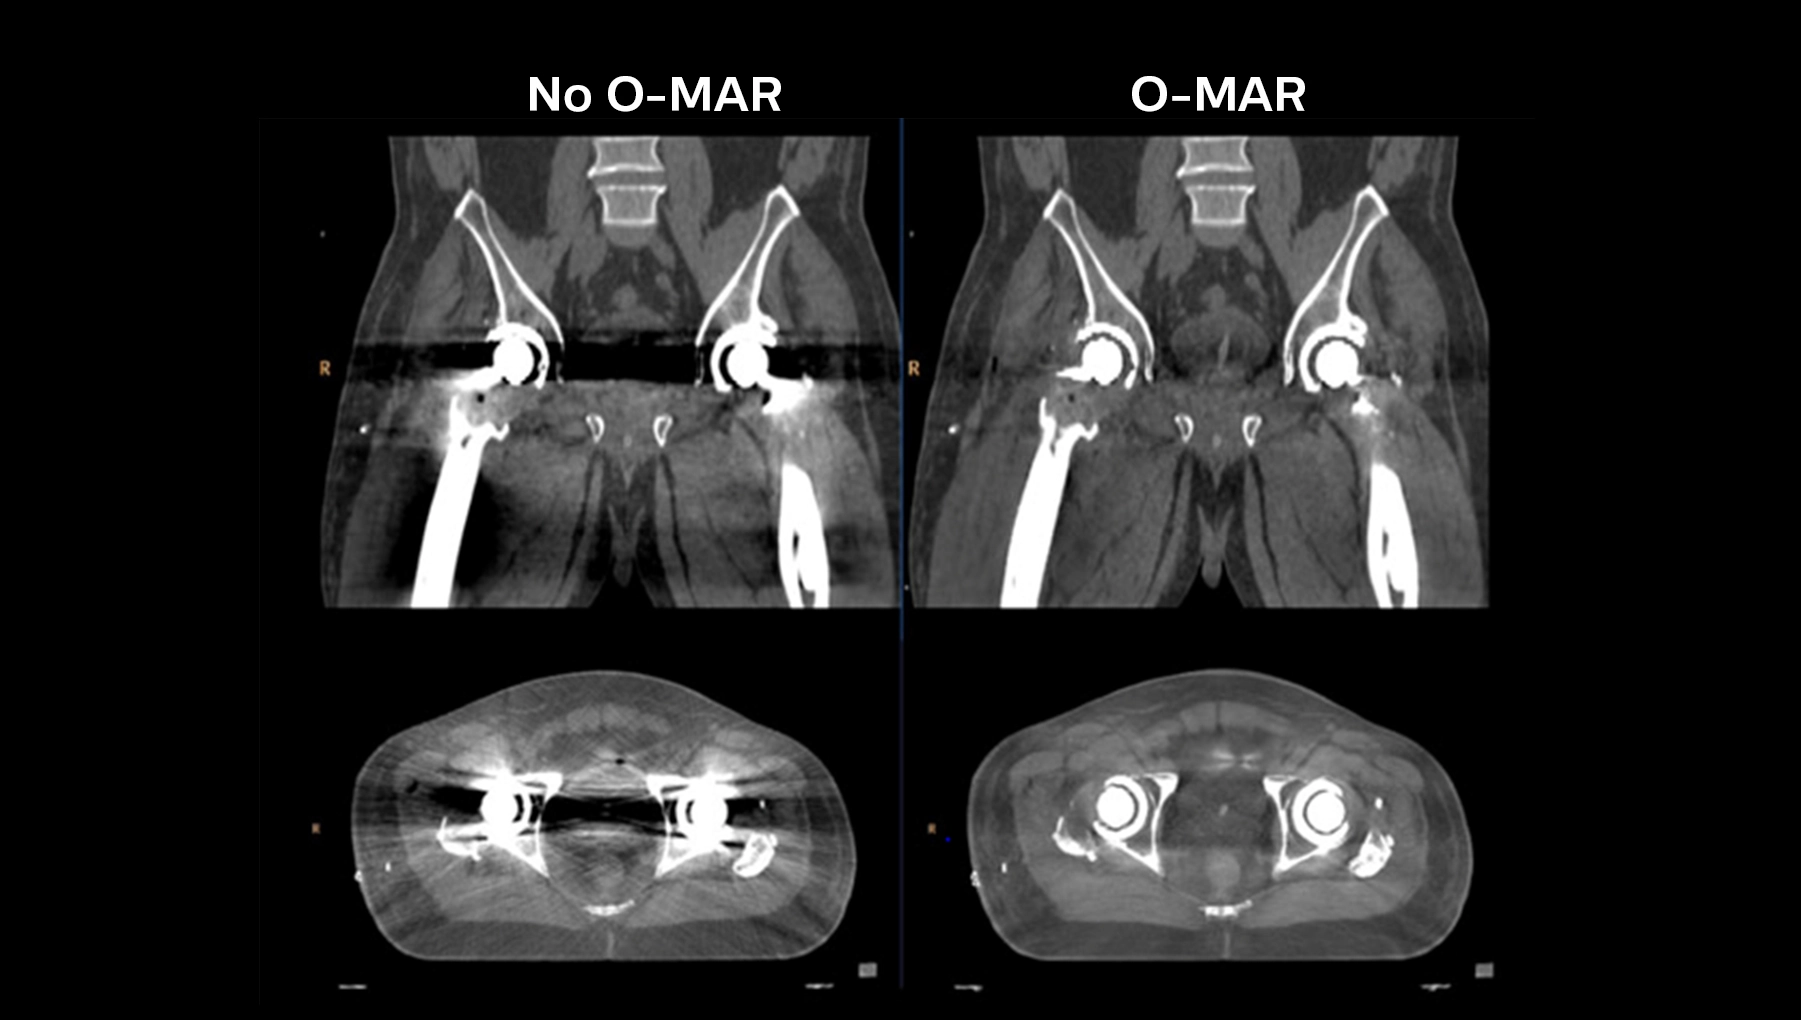

O-MAR (Orthopedic Metal Artifact Reduction)

- Комплексный алгоритм для снижения артефактов от эндопротезов, спиц, хирургических скоб и зондов,

- Существенно повышает точность КТ-контурирования в условиях металлоиндуцированных искажений, что критично для радиотерапии позвоночника и малого таза.